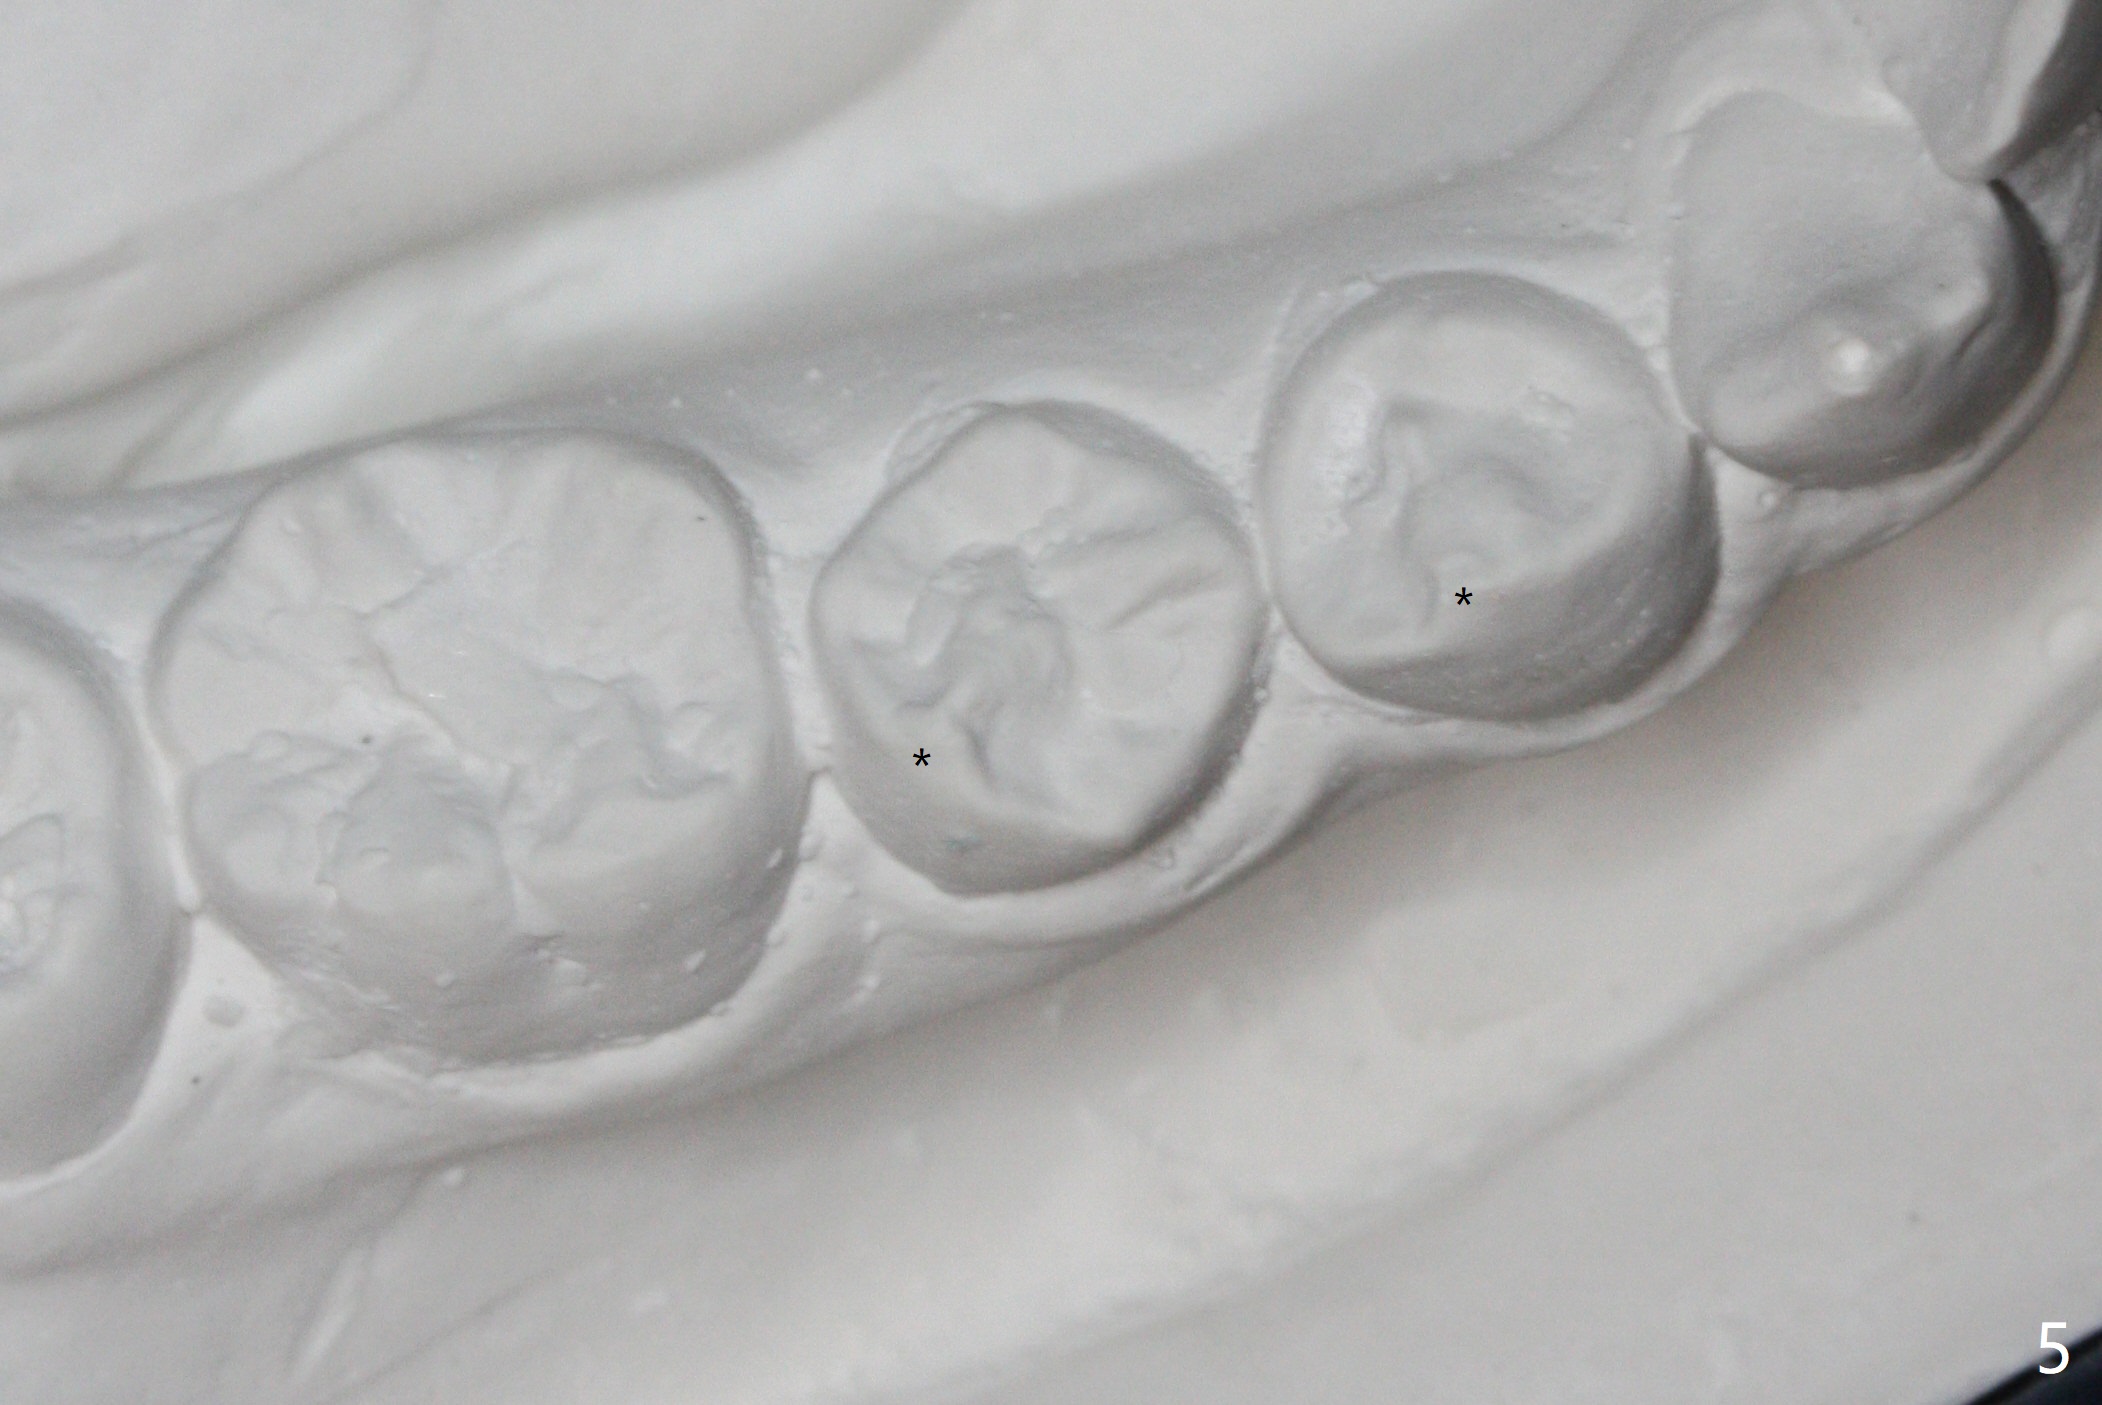

LR5 rotation appears to be associated with poor interdigitation on the right side (Fig.3), as compared to the left (Fig.4). * in Fig.3-6 indicates height of contour of a lower bicuspid, where a bracket should be placed.